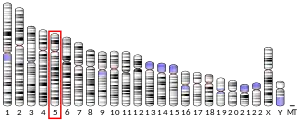

Transforming growth factor, beta-induced, 68kDa, also known as TGFBI (initially called BIGH3, BIG-H3), is a protein which in humans is encoded by the TGFBI gene, locus 5q31.[5][6]